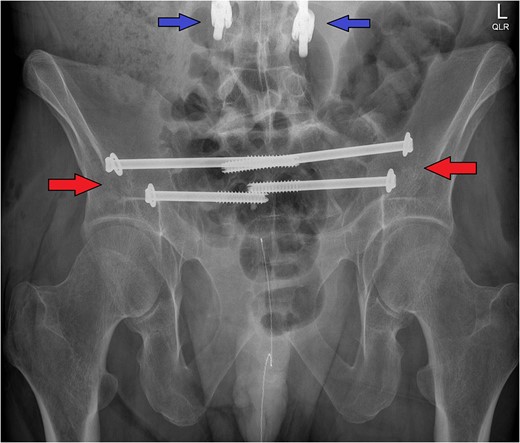

The post-operative X-ray pelvis shows the bilateral ilio-sacral fixation with percutaneous screws (red arrows). Note the inferior portion of the patient's pre-existing thoracolumbar instrumentation (blue arrows) that precluded spino-pelvic fixation as a viable surgical option in this case.

These injuries typically develop a characteristic deformity, with the sacrum and pelvis flexed in relation to the spine [5]. Multiple ilio-sacral screws did not correct the mild deformity already present, but did limit the risk of further progression and allow for early mobilization. Surgery was uneventful, and the patient was immediately much more comfortable. Mobilization was initiated with physiotherapy the following day: partial weight-bearing bilaterally with a frame.

In addition to diagnostic challenges, prior instrumented thoracolumbar fusion has potential implications with respect to treatment. If our case had been an isolated fracture, we might have opted for spino-pelvic fixation as the optimal operative management. However, given the biomechanical changes due to the patient's pre-existing thoracolumbar fixation the decision was made to only use ilio-sacral screws. Similar fractures in the past have reportedly been successfully treated with this technique [5].